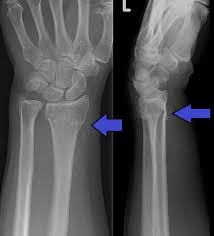

Facts About Broken Wrist Recovery Wrist Fracture Types Recovery

Facts About Broken Wrist Recovery Wrist Fracture Types Recovery from d33ljpvc0tflz5.cloudfront.net